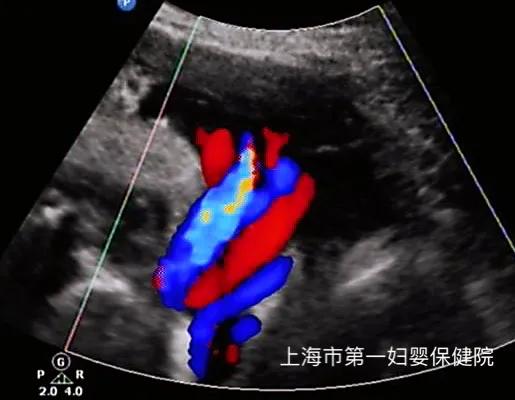

如果您看到我们超声报告上写着颈部见“U”形切迹,是脐带绕颈一圈;“W”形切迹,是脐带绕颈二圈;“锯齿状”切迹一般是三圈,也有更多圈的,在我们医院会在报告上写明,切迹的深度。

图中的宝宝脐带绕颈几周呢?在评论区给我留言吧[来看我][来看我][来看我][来看我]